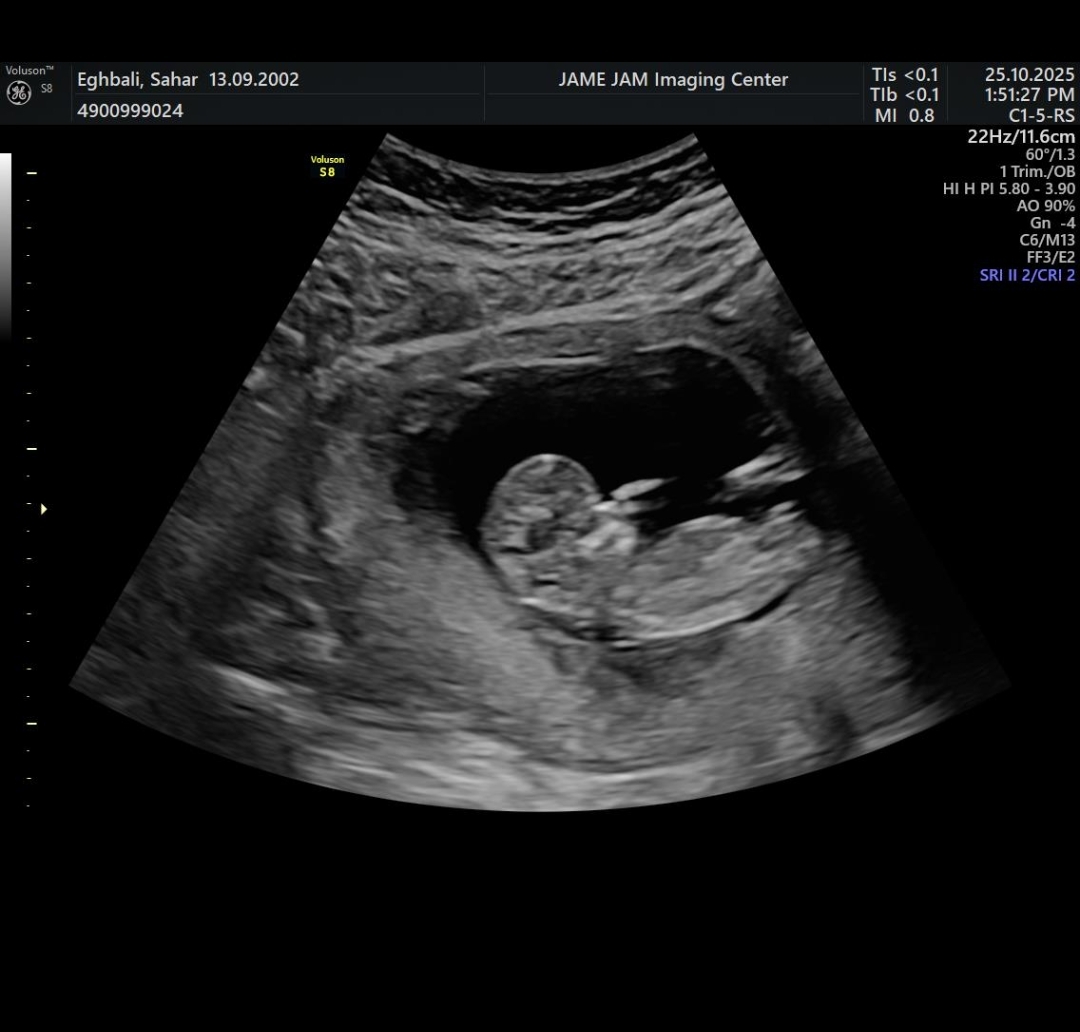

ممکنه جنسیت تو ان تی اشتباه گفته باشن

ببین توی ان تی اگه یه زائده کوچیک که در واقع رویش آلت پسرانه است رو ببینن جنسیت کامل معلوم میشه ولی ممکنه زاویه حوری باشه که دیده نشه اون موقع نظری نمیدن که دختره یا پسر

اسی جونم عکس سونو ان تی گذاشتم همه گفتن دختر

ولی ازمایش سلفری ک دقیق ترین روشه و خطاش ۱ درصده گفت پسر

نه عزیزم ان تی مشکوک تشخص داد منو فرستاد سلفری الان میخوام برم انومالی